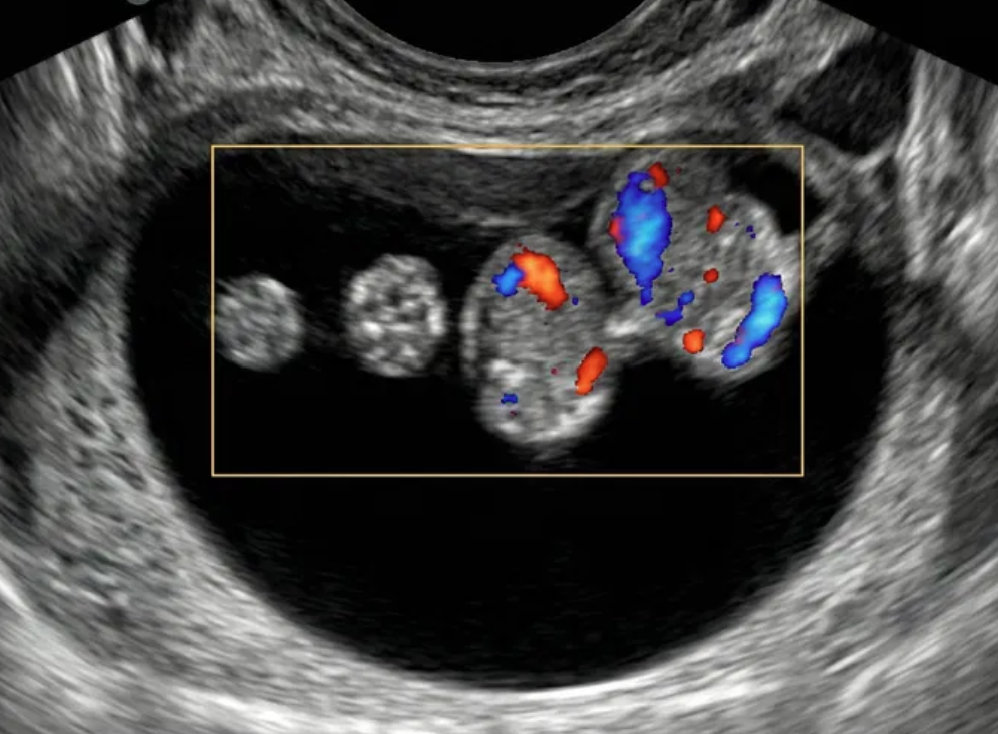

As regras simples do IOTA são um sistema de classificação baseado em características ultrassonográficas específicas que ajudam a distinguir massas anexiais benignas de malignas.

Classificação Benigna: Quando apenas regras benignas estão presentes (uma ou mais).

Classificação Maligna: Quando apenas regras malignas estão presentes (uma ou mais).

Classificação Indeterminada: Quando nenhuma regra está presente, ou quando há presença simultânea de regras benignas e malignas.